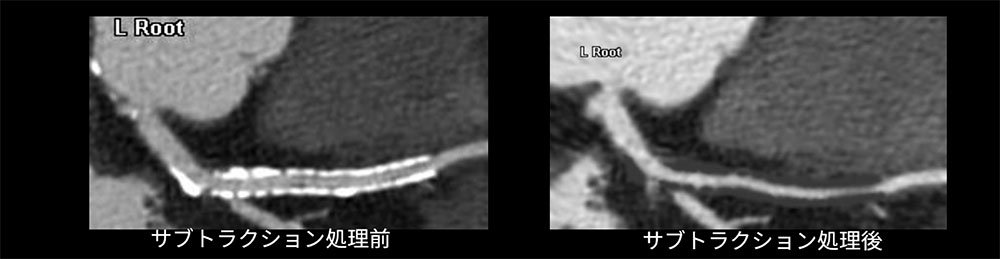

一方で、新たな取り組みとして、サブトラクション処理を行った画像の提示にも挑戦している。単純CT画像に対して、SnapShot Freeze 2.0処理を行うことにより、モーションアーチファクトのない画像が得られる。その結果、サブトラクション処理が可能となったため、石灰化病変やステント内腔の描出能向上が期待される(図2)。

RevolutionApexElite_Sakai03.jpg

図2) ステント挿入症例におけるサブトラクション処理